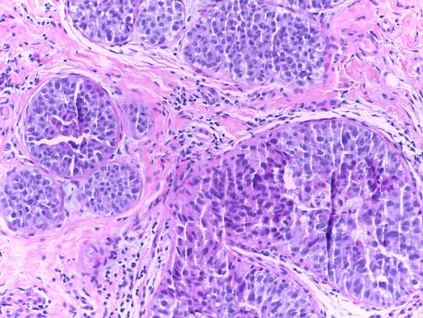

Background: Breast cancer has the highest prevalence in women globally. The classification and diagnosis of breast cancer and its histopathological images have always been a hot spot of clinical concern. In Computer-Aided Diagnosis (CAD), traditional classification models mostly use a single network to extract features, which has significant limitations. On the other hand, many networks are trained and optimized on patient-level datasets, ignoring the application of lower-level data labels. Method: This paper proposes a deep ensemble model based on image-level labels for the binary classification of benign and malignant lesions of breast histopathological images. First, the BreakHis dataset is randomly divided into a training, validation and test set. Then, data augmentation techniques are used to balance the number of benign and malignant samples. Thirdly, considering the performance of transfer learning and the complementarity between each network, VGG-16, Xception, Resnet-50, DenseNet-201 are selected as the base classifiers. Result: In the ensemble network model with accuracy as the weight, the image-level binary classification achieves an accuracy of $98.90\%$. In order to verify the capabilities of our method, the latest Transformer and Multilayer Perception (MLP) models have been experimentally compared on the same dataset. Our model wins with a $5\%-20\%$ advantage, emphasizing the ensemble model's far-reaching significance in classification tasks. Conclusion: This research focuses on improving the model's classification performance with an ensemble algorithm. Transfer learning plays an essential role in small datasets, improving training speed and accuracy. Our model has outperformed many existing approaches in accuracy, providing a method for the field of auxiliary medical diagnosis.